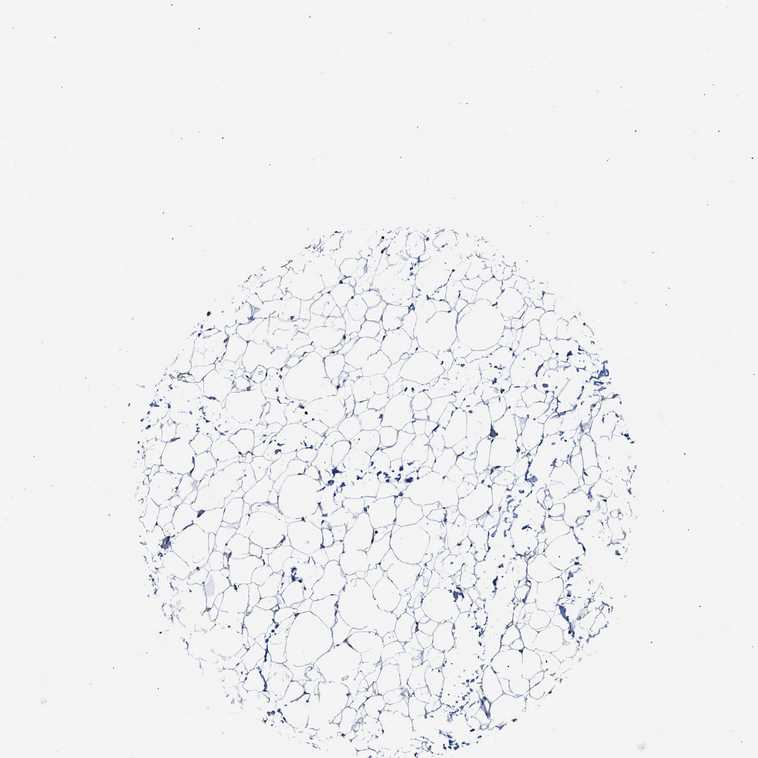

SOFT TISSUE 1 - Antibody stainingi

Antibody staining in the annotated cell types in the current human tissue is reported as not detected, low, medium, or high, based on conventional immunohistochemistry profiling in selected tissues. This score is based on the combination of the staining intensity and fraction of stained cells.

Each image is clickable and will lead to virtual microscopy that enables deeper exploration of all samples and also displays staining intensity scores, fraction scores and subcellular localization as well as patient and tissue information for each sample.

Antibody HPA017885

Chondrocytes Low

Fibroblasts Not detected

Peripheral nerve Not detected